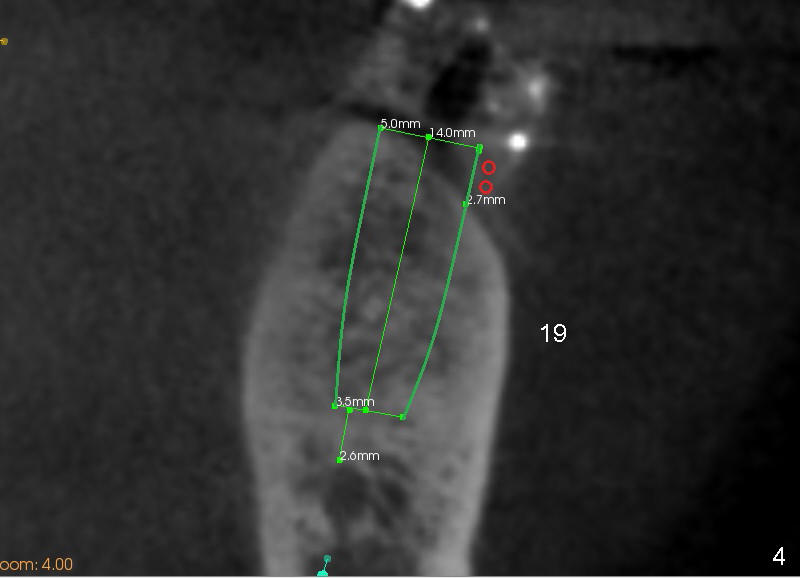

The lower left quadrant needs 3 implants (Fig.1,5: #19-21). The neighboring tooth #22 has periapical radiolucency (Fig.1 (CBCT sagittal section): *), which should be treated prior to implantation.

If primary stability is achieved for individual implants, they are splinted and loaded immediately.  Fig.2-4 are coronal sections.